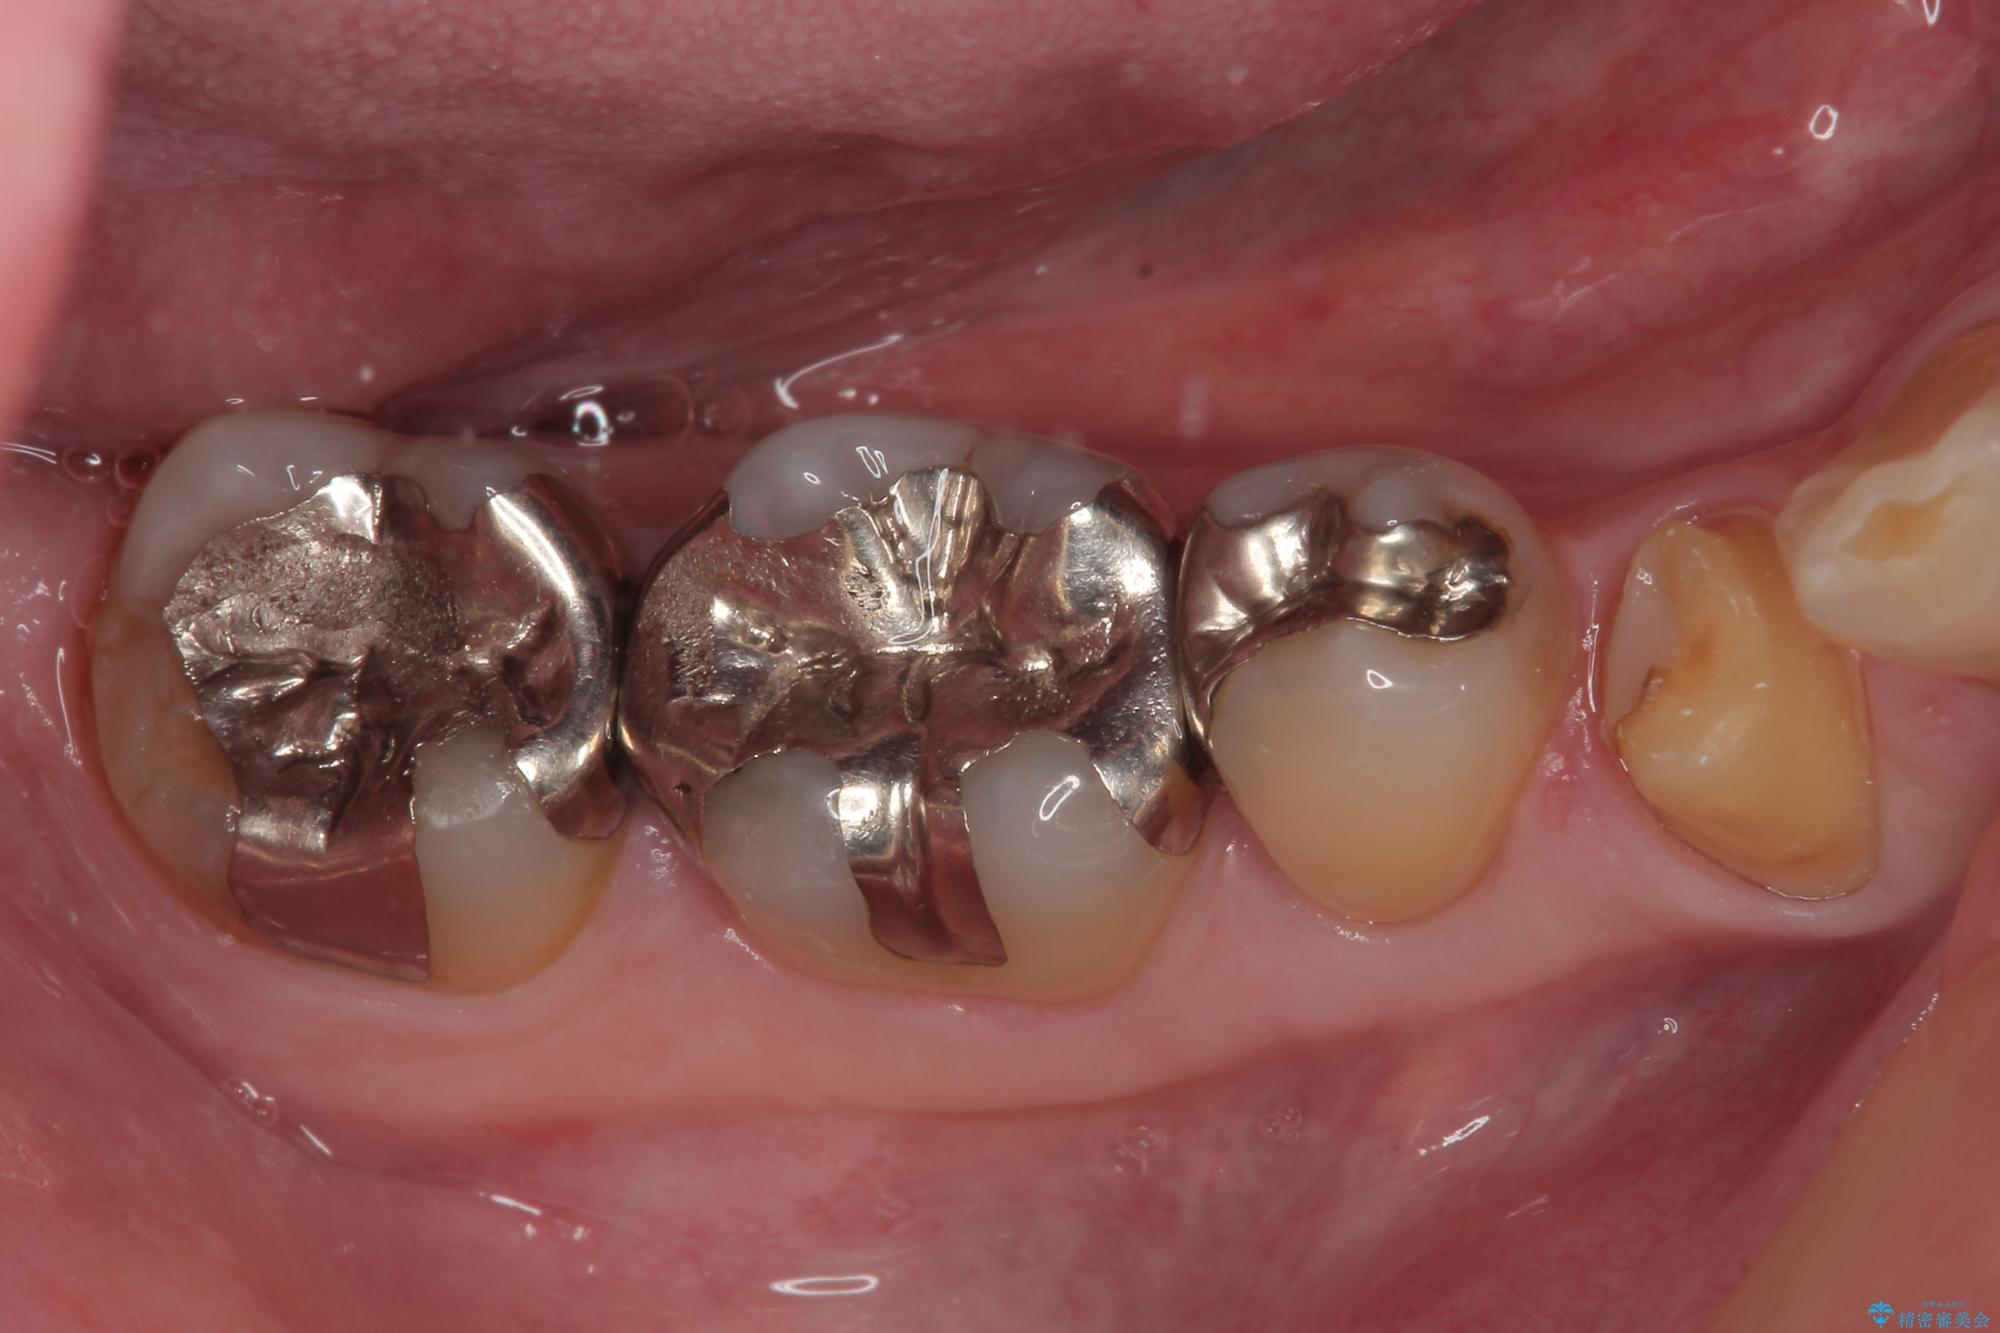

- 右下の銀歯が取れたとのことで来院された患者様です。以前にも取れていたところで、メタルインレーの不適合も認めていたため、次回外れたらオールセラミッククラウンにやり替えていくことを説明していたため、オールセラミッククラウンによる補綴治療を行っていくことにしました。

拡大鏡視野下で虫歯を除去しオールセラミッククラウンに適した形に整えました。

歯と歯茎の間に圧排糸と言われる糸を入れてシリコーン印象材にて型どりをしました。